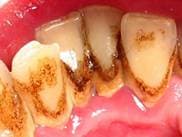

На фото: зубные отложения и воспаление десны при пародонтите средней степени.